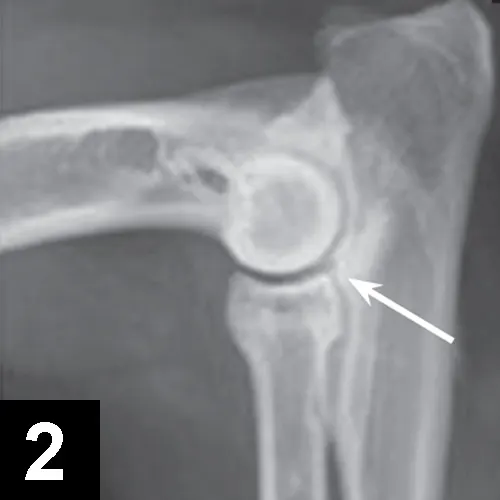

• Orthogonal radiographs may confirm diagnosis, especially with OCD lesions (Figures 1 and 2).

X-ray of a dog’s elbow with arrows pointing to lesions.

FIGURE 2

Mediolateral projection of the elbow: example of humeroradial and radioulnar incongruence and associated MCD. The arrow denotes a step lesion between the coronoid process of the ulna and the radial head. Note the subchondral sclerosis and the ill-defined border of the MCP.